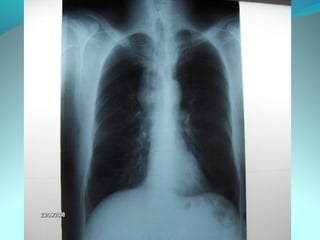

Cliché normal